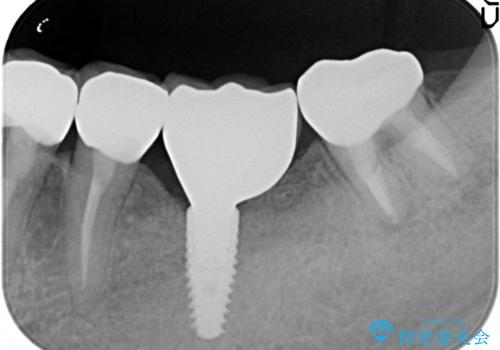

骨が薄い部位への骨造成をともなうインプラント

- 左下6番目の歯が欠損しており、インプラントで治療することとなりました。

骨の横幅が薄くなっており、インプラントを埋入するには骨幅が足りない状態でした。

まず最初に骨造成を行い、その後にインプラント埋入手術を行うこととなりました。

骨を増やすための手術が必要になるので、通常のインプラント治療より手術回数が一回多くなってしまうのがデメリットですが、将来的に安定したインプラントにするため、骨造成手術を前もって行いました。

しっかりとした骨幅を獲得し、理想的な太さのインプラントを埋入することができました。